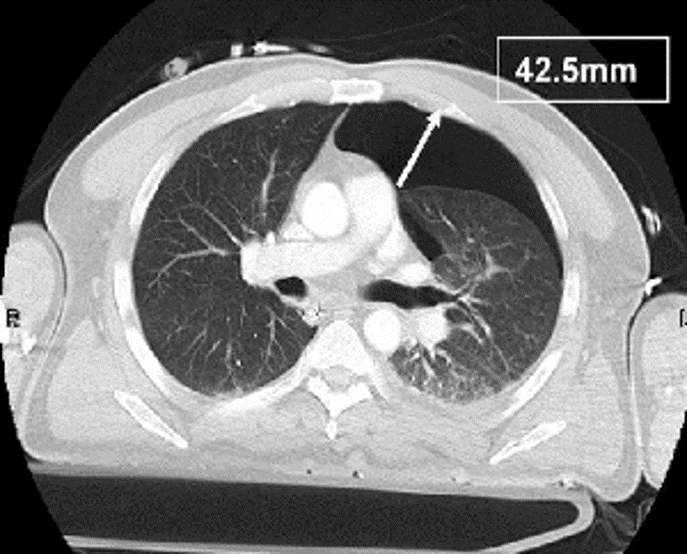

What is seen here?

Lung Bullae/Bleb

Spnt Pneumothorax

Blebs (pockets of air) in COPD pt